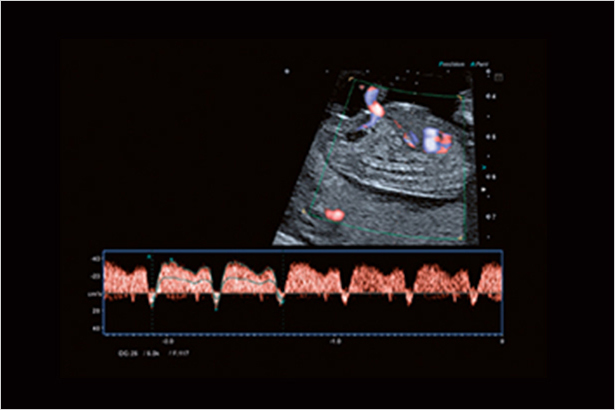

ADF運用寬頻帶窄脈沖技術讓多普勒成像模式具有敏感度和空間分辨率。